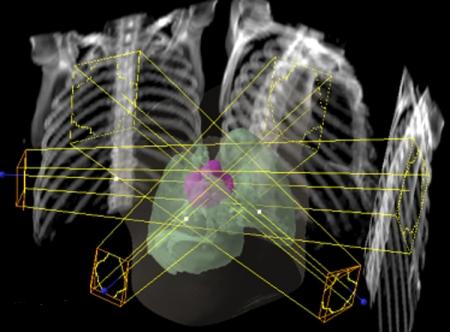

Effective treatment for carcinoma of the lung remains one of the biggest challenges in oncology. Radical radiotherapy may be a curative option for patients who are unsuitable for radical surgery either because of disease stage or because of co-morbidity. Long-term disease control with radical radiotherapy is disappointing with only about 6% of patients treated being alive at 5 years. Technological advances involved in the planning and delivery of radiotherapy may improve this. The advent of conformal radiotherapy, utilizing computed tomography and three-dimensional planning systems, allows much more accurate shaping of the radiation fields. This greater accuracy of target volume definition facilitates a reduction in the radiation dose to normal tissues, allowing for dose escalation to the tumour. Delineation of the target volume can be problematic. Conventional CT has limitations in term of distinguishing between benign and malignant tissues, e.g. the size criteria for involved lymph nodes. The oncologist uses a combination of radiological and clinical information when defining the target volume but their radiological interpretation of imaging is inferior to that of a radiologist. The Royal College of Radiologists (RCR) issued guidance in 2004 on the optimal imaging strategies for common cancers. These guidelines address issues regarding the localisation and staging of cancers and treatment planning, and also reporting and training. They recommend the development of closer links between radiologists and oncologists to optimise the interpretation of imaging and target volume definition. This article aims to briefly explain the planning process involved in irradiating lung cancers, highlight problematic areas and suggest ways in which co-operation with radiologists may improve the delivery of radiotherapy and therefore the treatment outcomes for this group of patients.

肺癌的有效治疗仍然是肿瘤学领域最大的挑战之一。对于因疾病分期或合并症而不适于根治性手术的患者,根治性放疗可能是一种治愈性选择。根治性放疗的长期疾病控制效果令人失望,接受治疗的患者中只有约6%能存活5年。放疗计划和实施过程中的技术进步可能会改善这一情况。适形放疗的出现,利用计算机断层扫描和三维计划系统,能够更精确地塑造辐射野。靶区定义的更高准确性有助于减少对正常组织的辐射剂量,从而可以提高肿瘤的照射剂量。靶区的勾画可能存在问题。传统CT在区分良性和恶性组织方面存在局限性,例如受累淋巴结的大小标准。肿瘤学家在定义靶区时会综合运用放射学和临床信息,但他们对影像的放射学解读不如放射科医生。英国皇家放射科医师学院(RCR)在2004年发布了关于常见癌症最佳影像策略的指南。这些指南涉及癌症的定位、分期和治疗计划等问题,以及报告和培训。它们建议放射科医生和肿瘤学家建立更紧密的联系,以优化影像解读和靶区定义。本文旨在简要解释肺癌放疗的计划过程,突出存在问题的领域,并提出与放射科医生合作可能改善放疗实施从而提高这类患者治疗效果的方法。